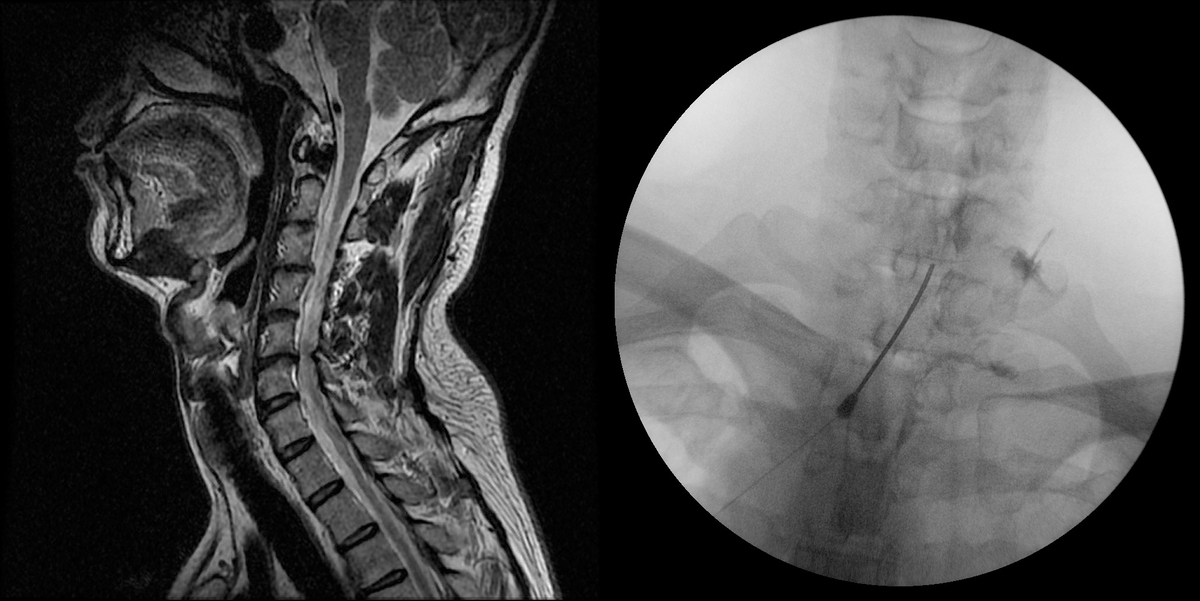

목 디스크는 조기 발견 시 비수술적 치료만으로도 충분히 호전될 수 있다. 초기에는 약물치료나 물리치료, 도수치료를 통해 염증을 줄이고 근육 긴장을 완화시킨다. 그러나 통증이 심하거나 4주 이상 보존적 치료에도 호전이 없다면 비수술 치료를 고려하게 된다. 대표적인 방법으로는 신경차단술과 신경성형술이 있다.

신경차단술은 염증과 부종이 생긴 신경 주위에 특수 주사바늘을 이용해 약물을 주입해 통증을 완화시키는 치료법이다. 반면 신경성형술은 꼬리뼈를 통해 지름 1mm의 카테터를 삽입해 통증의 원인 부위에 직접 약물을 투여하고, 염증을 제거하면서 신경 주변의 유착을 박리하는 시술이다.

두 방법 모두 절개가 필요 없고 국소마취로 진행되며, 흉터나 출혈이 거의 없다. 또한 시술 시간이 짧고, 고혈압·당뇨 등 만성질환자도 치료가 가능하다는 장점이 있다.